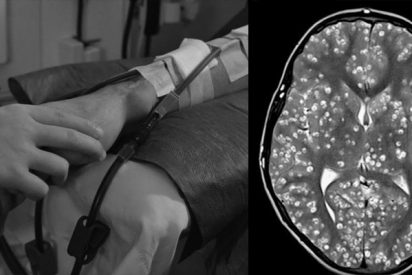

Un joven muere por culpa de una plaga de gusanos en el cerebro

Médicos indios descubrieron el cerebro de un joven de 18 años plagado de quistes causados por un parásito porcino. El muchacho, al que los doctores no pudieron salvarle la vida, acudió al servicio de urgencias de la ciudad de Faridabad, en el estado de Haryana, aquejado de fuertes dolores de cabeza y convulsiones.